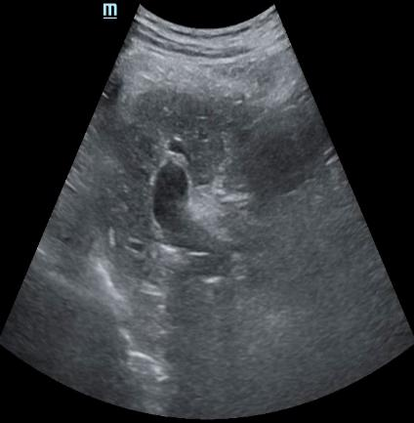

Most deep neural networks (DNNs) based ultrasound (US) medical image analysis models use pretrained backbones (e.g., ImageNet) for better model generalization. However, the domain gap between natural and medical images causes an inevitable performance bottleneck. To alleviate this problem, an US dataset named US-4 is constructed for direct pretraining on the same domain. It contains over 23,000 images from four US video sub-datasets. To learn robust features from US-4, we propose an US semi-supervised contrastive learning method, named USCL, for pretraining. In order to avoid high similarities between negative pairs as well as mine abundant visual features from limited US videos, USCL adopts a sample pair generation method to enrich the feature involved in a single step of contrastive optimization. Extensive experiments on several downstream tasks show the superiority of USCL pretraining against ImageNet pretraining and other state-of-the-art (SOTA) pretraining approaches. In particular, USCL pretrained backbone achieves fine-tuning accuracy of over 94% on POCUS dataset, which is 10% higher than 84% of the ImageNet pretrained model. The source codes of this work are available at https://github.com/983632847/USCL.